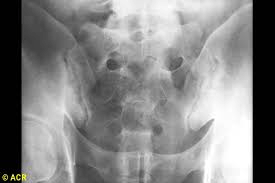

22 Yo M presents with three weeks of low back pain, most notable at night and early in the morning, better with activity.

This patient has sacroilitis (Ank Spond)

start NSAIDs

inflammatory low back pain DDx

Spondoarthropathies (PAIR)

complications: require hip replacements (Ank Spond), enthesopathy (heel/rib pain), uveitis (painful red eye), cauda equina, amyloidosis, aortic insufficiency